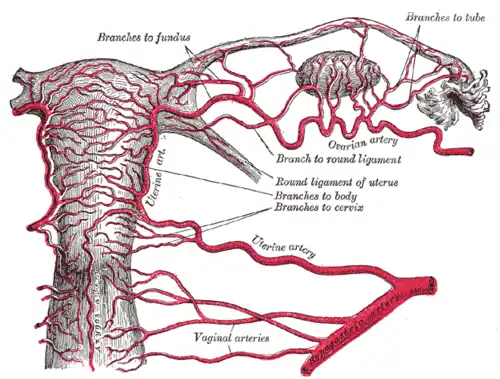

Irrigación

- Arterias tubáricas laterales de la arteria ovárica (proveniente de la aorta abdominal)

- Arterias tubáricas mediales de la arteria uterina (proveniente de la arteria iliaca interna o hipogástrica)

Se describe una anastomosis entre estas dos arterias en el borde del útero, a la altura del ligamento redondo.